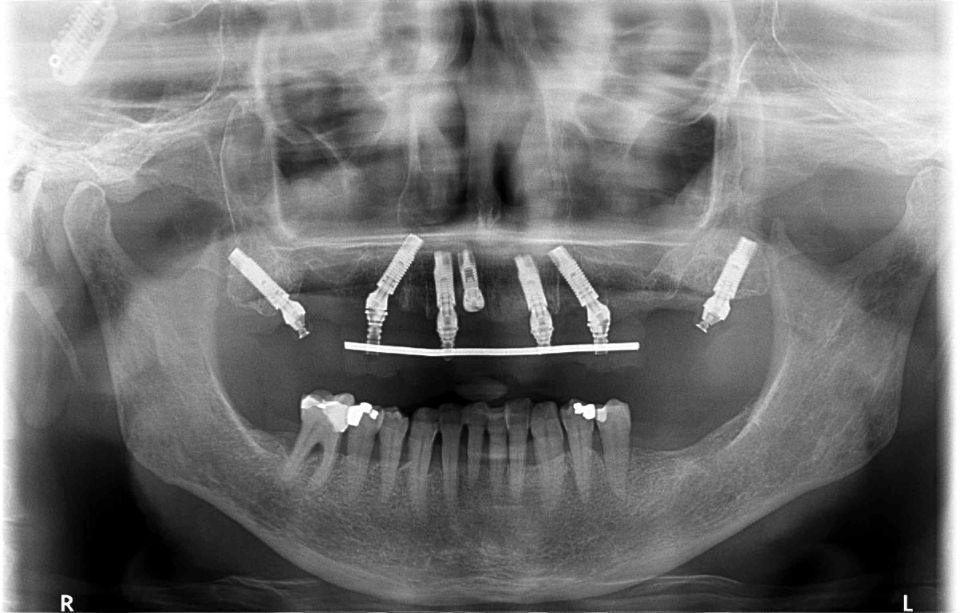

Implantologia bucal

La implantologia és l´especialitat odontològica que s´ocupa de la substitució de l´arrel de la dent perduda.

La substitució es fa mitjançant una petita intervenció quirúrgica per col·locar una peça de titani dins de l'os maxil·lar.

L'implant té una rosca al seu interior on posteriorment s'enroscarà el pilar que suportarà la corona protètica.

La demora en la reposició de dents comporta alteracions funcionals i anatòmiques de l'aparell buc dental, com ara: la reabsorció de l'os maxil·lar, migracions i desplaçaments de dents romanents o alteracions fonètiques, estètiques, masticatòries, etc...

Després de la valoració de l'implantòleg i un diagnòstic molt acurat per part de l'equip professional, es plantegen diferents solucions. Depenent del problema plantejat que pot ser: pèrdua unitària, pèrdua múltiple o desdentat complet...es realitzarà la tècnica precisa per tal de millorar la qualitat de vida del pacient.

La implantologia és una de les àrees mèdiques que més ha evolucionat en els darrers anys. Això fa que la fiabilitat i la comoditat del pacient augmenti.

De la mateixa manera oferim cirurgies implantològiques amb flux digital, utilitzant fèrules quirúrgiques personalitzades; permetent disminuir temps quirúrgics i mantenint la precisió en els tractaments.